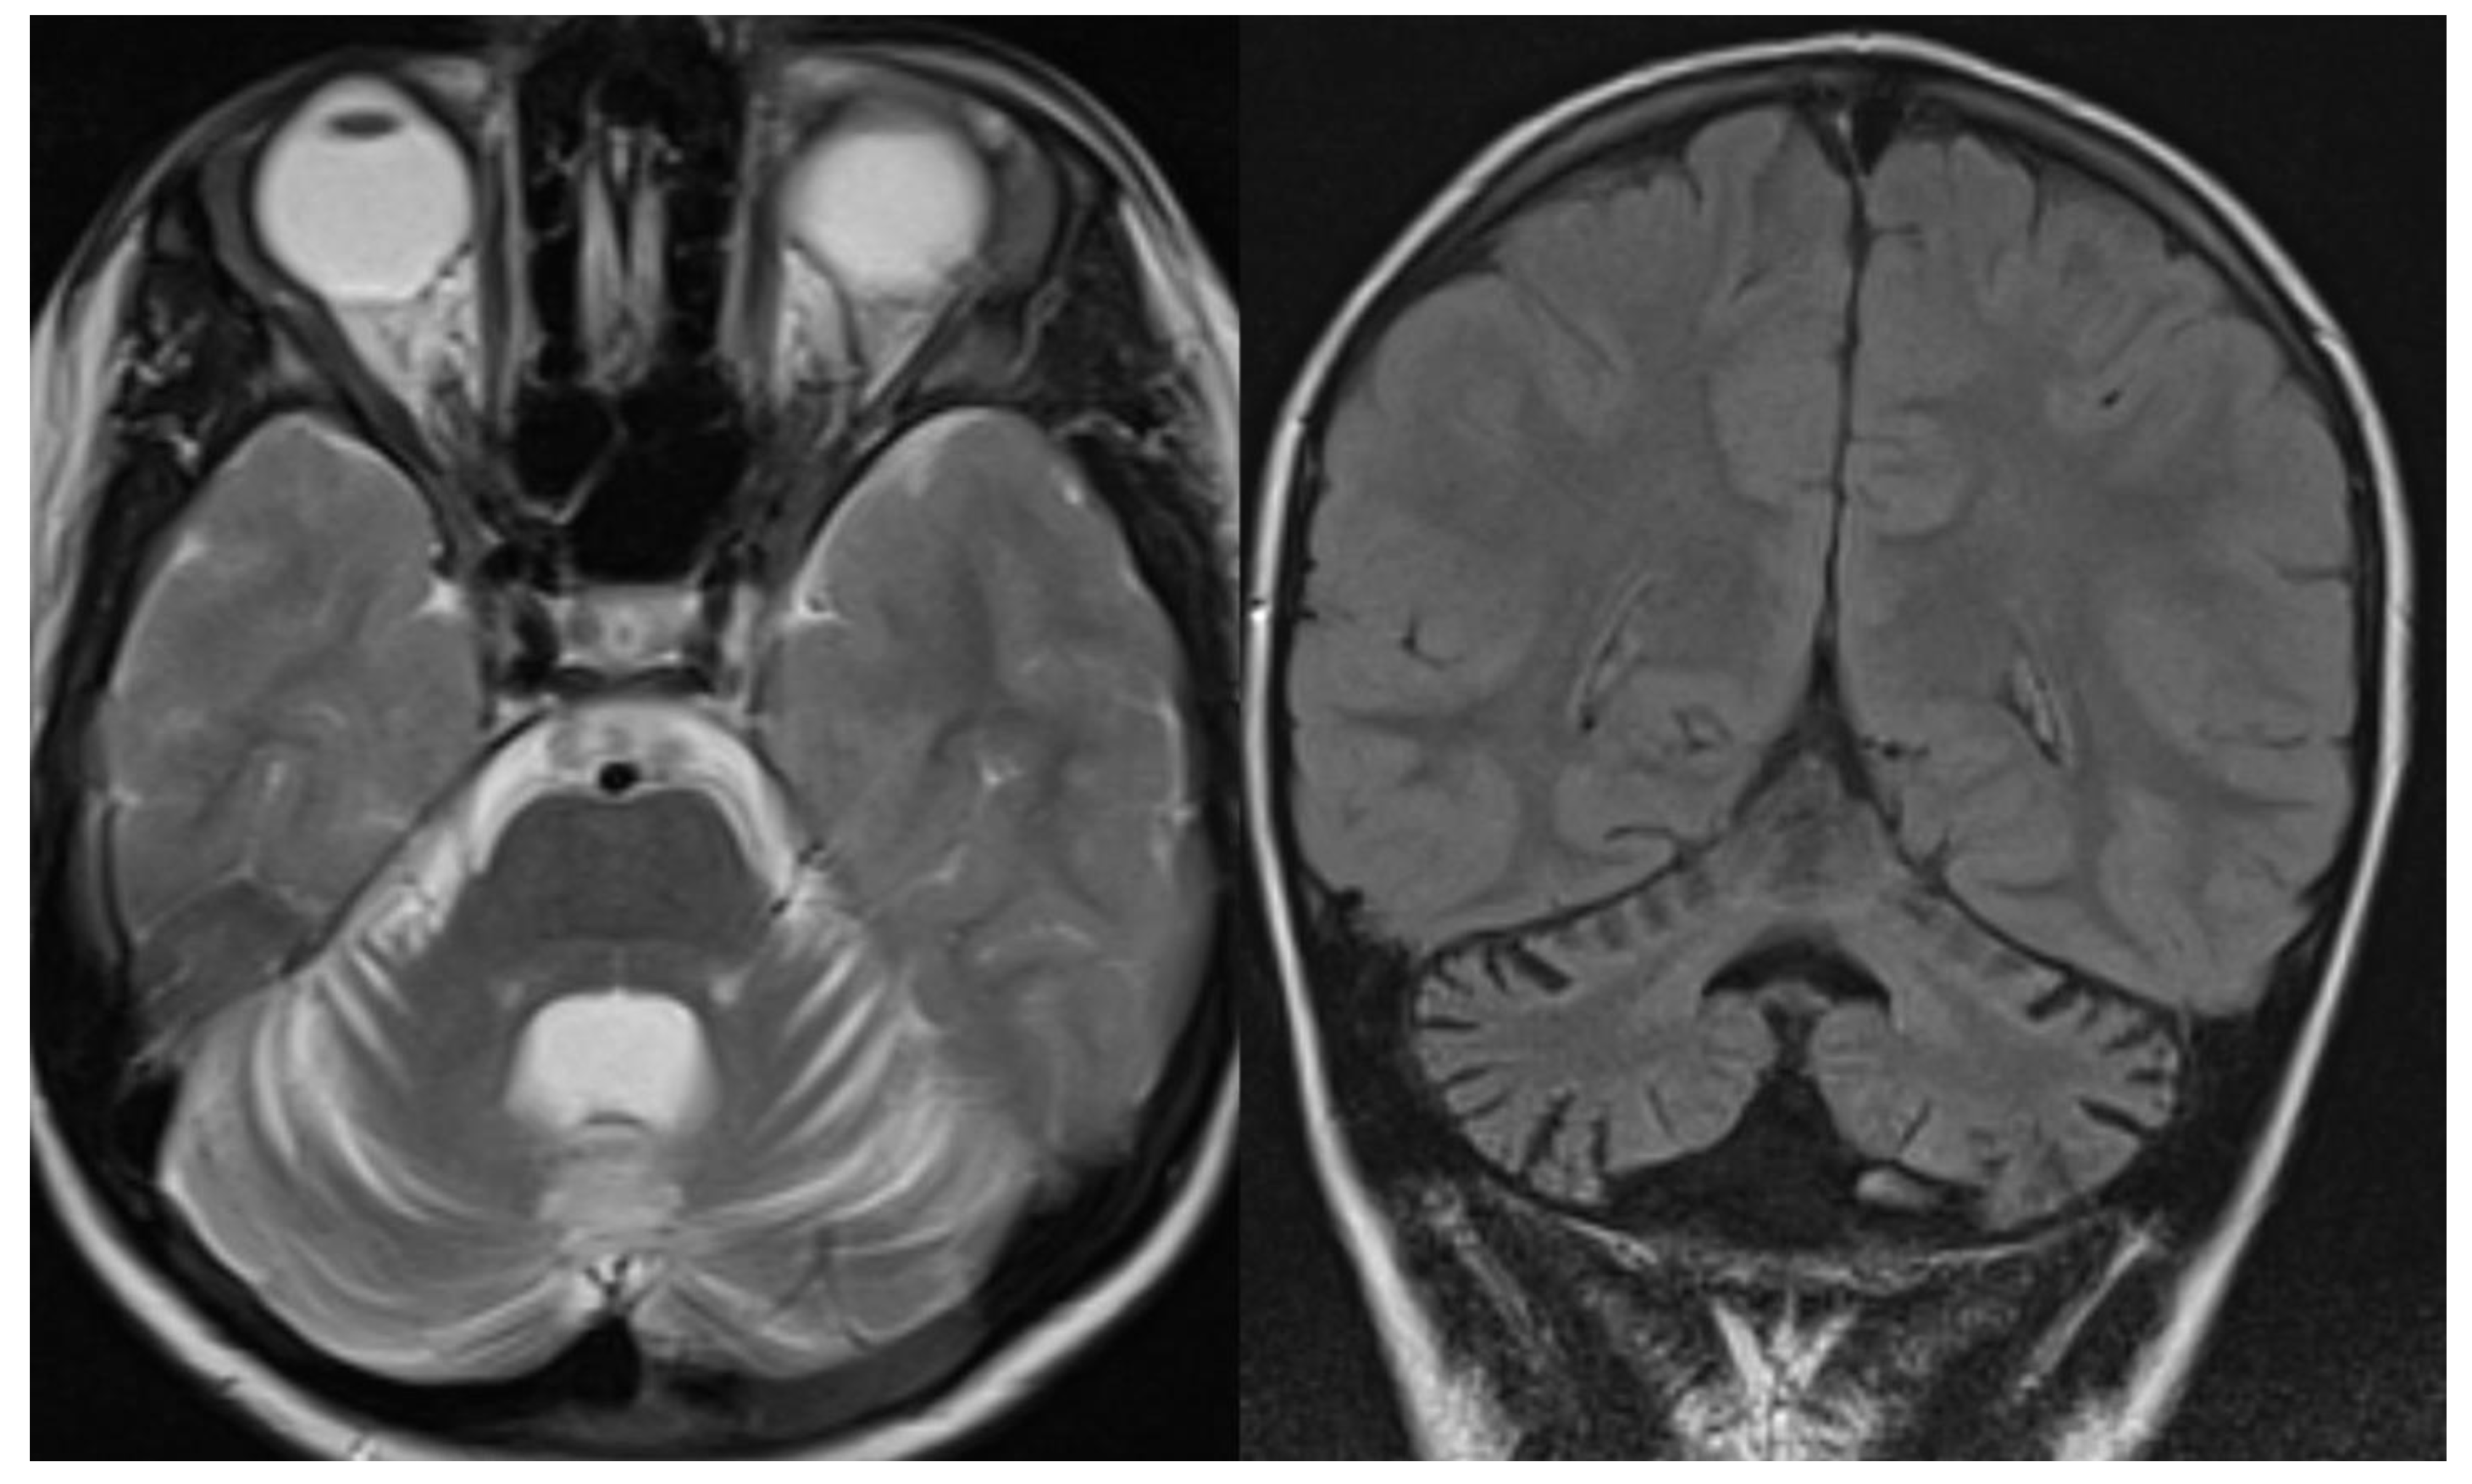

Overall, MRI in PCH patients shows a variable degree of cerebellar hypoplasia with involvement of pons and cerebrum. On coronal imaging, the particular shape of the cerebellum, named “dragonfly” or “butterfly” appearance, was described by Barth et al. [6]. The cerebellar hemispheres are particularly atrophic, with a substantial sparing of the vermis. Flattening of the caudate nuclear heads can be present [5]. Additional inconstant findings are cerebellar cysts (PCH 1, 2, and 6), agenesis of the corpus callosum (PCH 9), simplified gyral pattern (PCH 6 and 10), and hypomyelination (PCH 1, 2, 6, and 9). In several PCH, pons could be relatively preserved, and in PCH10, the cerebellum is mostly normal 11. The presence of C-shaped inferior olive has been reported in PCH2, suggesting a prenatal onset 9 (Figure 1).

Figure 1.

PCH 2. Brain MRI scan of a 1-year-old girl with TSEN 54 mutation. MR images demonstrate the characteristic “dragonfly-like” cerebellar pattern: severe hypoplasia of the cerebellar hemispheres with a relative sparing of the vermis. Note the flat ventral surface of the pons and thin corpus callosum.